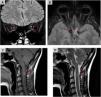

The aim of this work is to provide a diagnostic approach to the potential causes of optic neuropathy, focusing on the radiological findings associated with this pathology. Various etiologies have been identified, including inflammatory and demyelinating optic neuritis, developmental and hereditary diseases, neurodegenerative disorders, infectious conditions, post-traumatic causes, ischemic optic neuropathy (with anterior ischemic optic neuropathy being the most common form), and neoplastic etiologies. Optical coherence tomography and magnetic resonance imaging play a fundamental role in the diagnosis of optic neuropathy, allowing to distinguish patterns of optic nerve involvement. These studies are essential to locate and characterize the different pathologies, increasing the precision of the diagnosis in diseases presenting optic neuropathy as the main symptom. In conclusion, the findings obtained from magnetic resonance imaging are essential in the differential diagnosis of optic nerve diseases, aiding in the localization and characterization of various pathologies affecting either the optic pathway alone or multiple levels of the central nervous system and thereby increasing diagnostic accuracy.